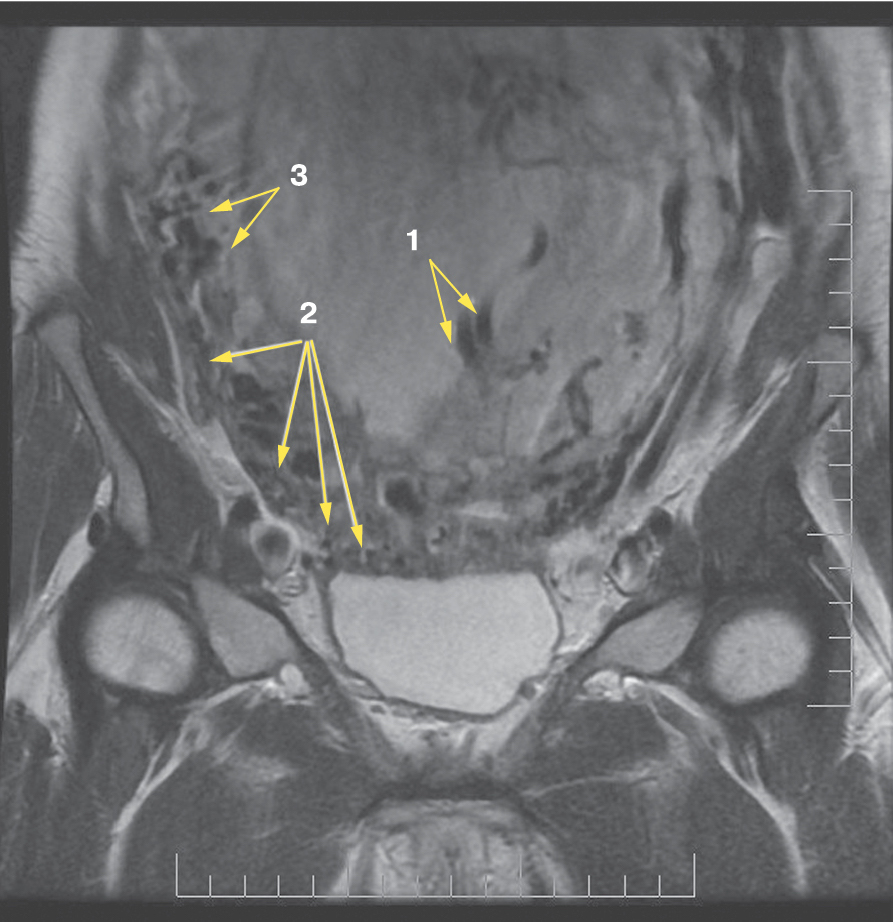

Рис. 5. Корональная проекция МРТ. 1 – интрамуральная гиперваскуляризация; 2- измененный контур мочевого пузыря

Рис. 6. Корональная проекция МРТ. 1 – обнаженный сосуд; 2 – интрамуральная гиперваскуляризация; 3 – гиперваскуляризация плаценты

Является ли симптом «обнаженного сосуда» патогномоничным для параметральной инвазии или нет, еще предстоит выяснить; однако в ходе исследования установлена его связь с частотой гистерэктомий в группах с наличием симптома «обнаженного сосуда», что, вероятно, обусловлено мощной сосудистой сетью коллатералей и неоангиогенезом. Во всех случаях обнаружения данного признака впоследствии была выполнена вынужденная гистерэктомия (рис. 3–6, пациентка Н., 37 лет).